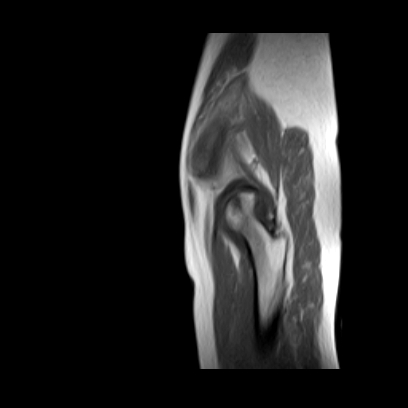

请看看我的片子,我得的什么病,该怎么治疗?谢谢[img][/img]

片子不全,应该是左侧股骨头无菌坏死,右侧似乎没问题,到正规医院治疗,千万别看广告去小医院,吃中药什么的,都是骗人的(说了也白说,百分百都得让人骗点钱才甘心。)

应该是左侧股骨头无菌坏死